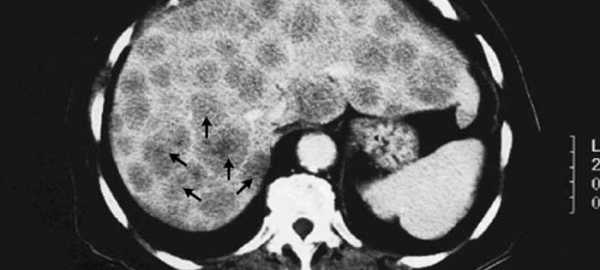

УЗИ — простой, эффективный метод диагностики, не требующий больших затрат. Метастазы при УЗИ выглядят как эхогенные очаги. Для диагностики метастазов в печень особенно эффективно интраоперационное УЗИ.

При АГ метастазы имеют вид очагов с низким поглощением облучения. Метастазы из толстой кишки обычно имеют крупный бессосудистый центр с накоплением контрастного вещества по периферии в виде кольца. Приблизительно у 29% больных, которым произведена резекция толстой кишки по поводу рака, при КТ обнаруживают скрытые метастазы в печень. Отсроченное накопление контрастного вещества повышает частоту выявления метастазов. Применяют также КТ с контрастированием йодолиполом.

МРТ в T1-режиме — лучший метод выявления метастазов рака толстой кишки в печень. Т2-взвешенные изображения выявляют отёк прилежащей к очагам метастазов участков ткани печени.

МРТ с введением оксида железа или гадолиния имеет большую чувствительность. Дуплексное цветное допплеровское УЗИ выявляет менее выраженный застой в воротной вене, чем при циррозе печени и портальной гипертензии.